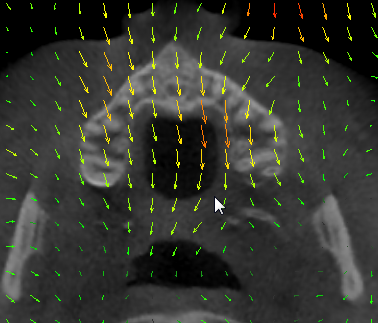

You can assess the resulting transform using Transforms module.

There are many visualization options, you can see displacement vector value at current mouse pointer position in “Information” section. You can compute average displacement in regions defined by segments (created in Segment Editor) by computing Segment Statistics on displacement magnitude image (created in Transforms module / Convert, Magnitude only => checked, Apply).